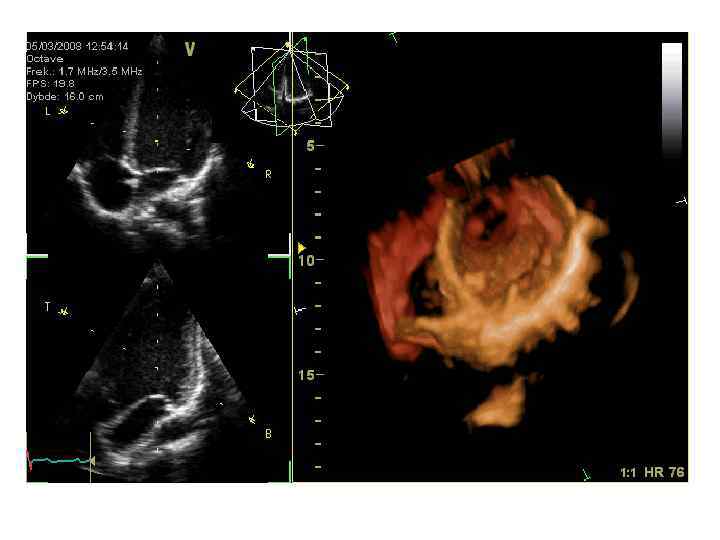

Областная клиническая больница г. Белгород Ультразвуковое исследование сердца в ОКБ проводится на одной из лучших эхокардиографических систем «VIVID-7»

Областная клиническая больница г. Белгород Ультразвуковое исследование сердца в ОКБ проводится на одной из лучших эхокардиографических систем «VIVID-7»

Ультразвуковое исследование сердца (эхокардиография)

Ультразвуковое исследование сердца (эхокардиография)

• Интенсивное развитие и совершенствование медицинской ультразвуковой техники основано на использовании научных основ радио- и гидролокации, цифровой электроники, полупроводниковой техники. • Современные медицинские ультразвуковые сканеры позволяют получать трехмерные изображения объектов с разрешающей способностью до 0, 1 мм, • Допплеровские методики позволяют оценивать кровоток в сосудах, движение стенок сердца и других тканей тела человека со скоростями менее 1 см/с.

• Интенсивное развитие и совершенствование медицинской ультразвуковой техники основано на использовании научных основ радио- и гидролокации, цифровой электроники, полупроводниковой техники. • Современные медицинские ультразвуковые сканеры позволяют получать трехмерные изображения объектов с разрешающей способностью до 0, 1 мм, • Допплеровские методики позволяют оценивать кровоток в сосудах, движение стенок сердца и других тканей тела человека со скоростями менее 1 см/с.